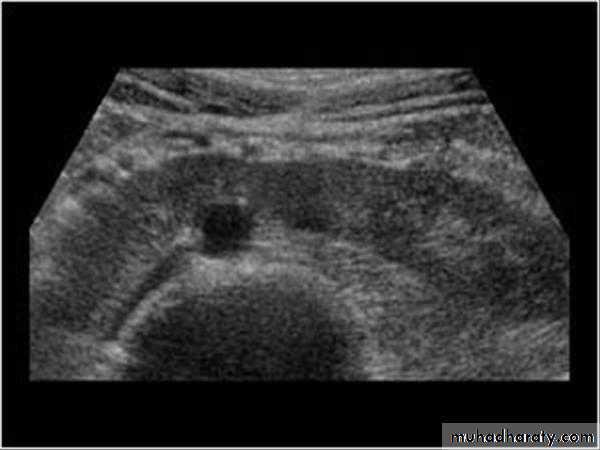

Ultrasound findings:

Division of renal sinus

Ultrasound shows enlarged lobulated kidneys full of cysts of variable size.